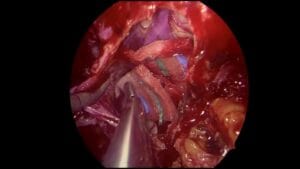

Epistaxis

En este caso, el Dr. André Felippu realiza la ligadura de la arteria esfenopalatina para controlar el sangrado nasal.